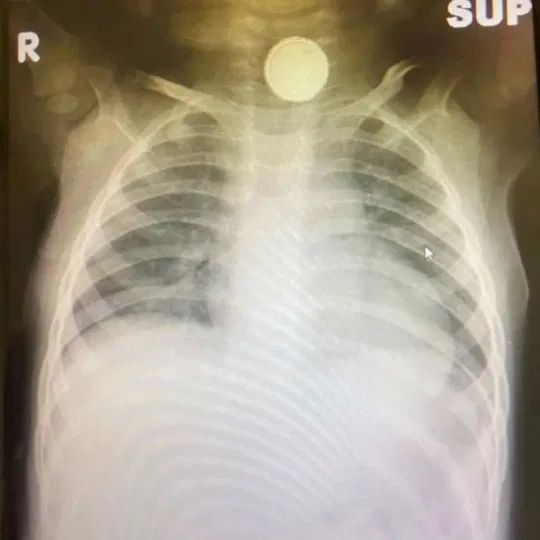

Dwultenia Sofia-Grace trafiła do szpitala po tym, jak jej tata Calham zauważył, że dziewczynka ma problemy z jedzeniem, piciem i oddychaniem. Po wstępnym badaniu lekarze zlecili badanie RTG. Na zdjęciu rentgenowskim wyraźnie widać było ciało obce w przełyku dziecka. Niestety nie dało się go wyciągnąć bez interwencji chirurgicznej.

Bateria w przełyku Sofii

Bateria w przełyku Sofii © Facebook